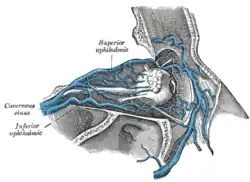

Veins of orbit. (Central retinal vein not labeled, but region is visible - the vein is inside the optic nerve.) | |

| Drains to | Superior ophthalmic vein or cavernous sinus |

The central retinal vein drains into either the superior ophthalmic vein or the cavernous sinus.[1]

The central retinal vein varies between individuals.[3] in some the central retinal vein drains into the superior ophthalmic vein, and in some it drains directly into the cavernous sinus.[3][4]